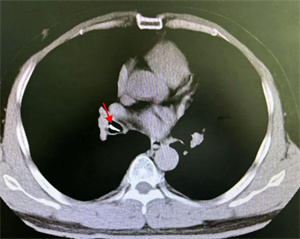

白主任还邀请消化内科副主任吴斌、胸外科许涛医生一同到场,齐心协力保障患儿。然而,白主任用支气管镜反复多次查找,却始终没有发现异物,同时使用小探头超声内镜扫描,也一无所获。考虑有移位可能,白主任果断建议床旁摄片,进行气管镜下定位。时间紧迫,影像科技师汪津立刻带着机器来到气管镜室。经过摄片,发现金属异物显影在了胃泡里!